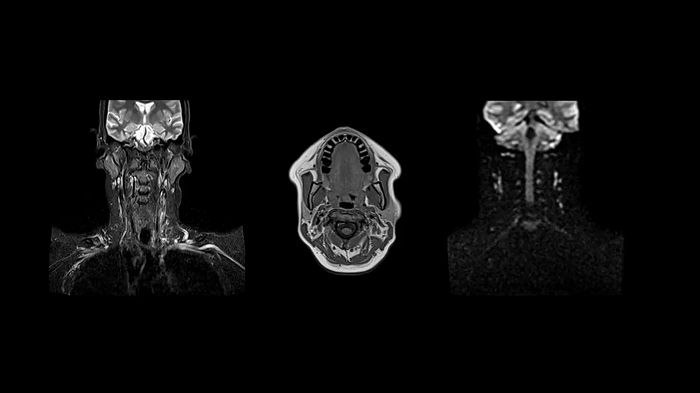

Neck

Excellent soft tissue contrast in the neck

All-inclusive soft tissue examination of the head with outstanding image quality for T1, T2, and diffusion contrast.

• Head/Neck Coil

• Spine Coil

80 cm bore MAGNETOM Free.Max

Image Courtesy: University Hospital Erlangen, Germany | Image-ID: 4aaaa0458

Time-of-flight angiography

Non-contrast enhanced angiography of the cranial vessels is used to detect vessel occlusions or aneurysms. High-resolution ToF angiography can also show small arteries for subtle diagnoses.

Image Courtesy: University Hospital Erlangen, Germany | Image-ID: 4aaaa0466